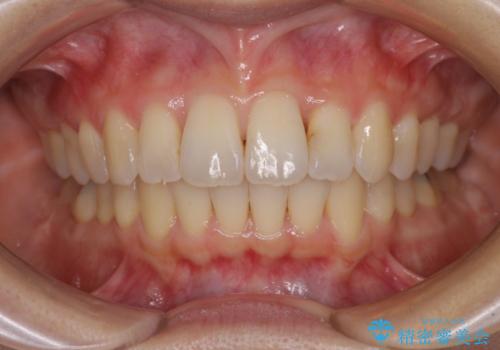

1日22時間の装着時間をしっかり守ってくださったので、1年程度で治療を終えることができました。

1セットのマウスピースで概ね治療を終えたのですが、前歯僅かな叢生が残ったため、2セット目のマウスピースで仕上げました。

気にしていた口元の印象が改善され、患者様には大変満足していただきました。